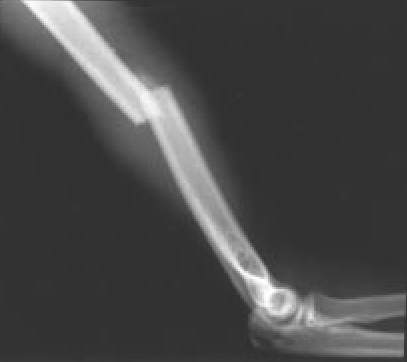

Fig. 3A.: Fractura transversa del tercio medio humeral